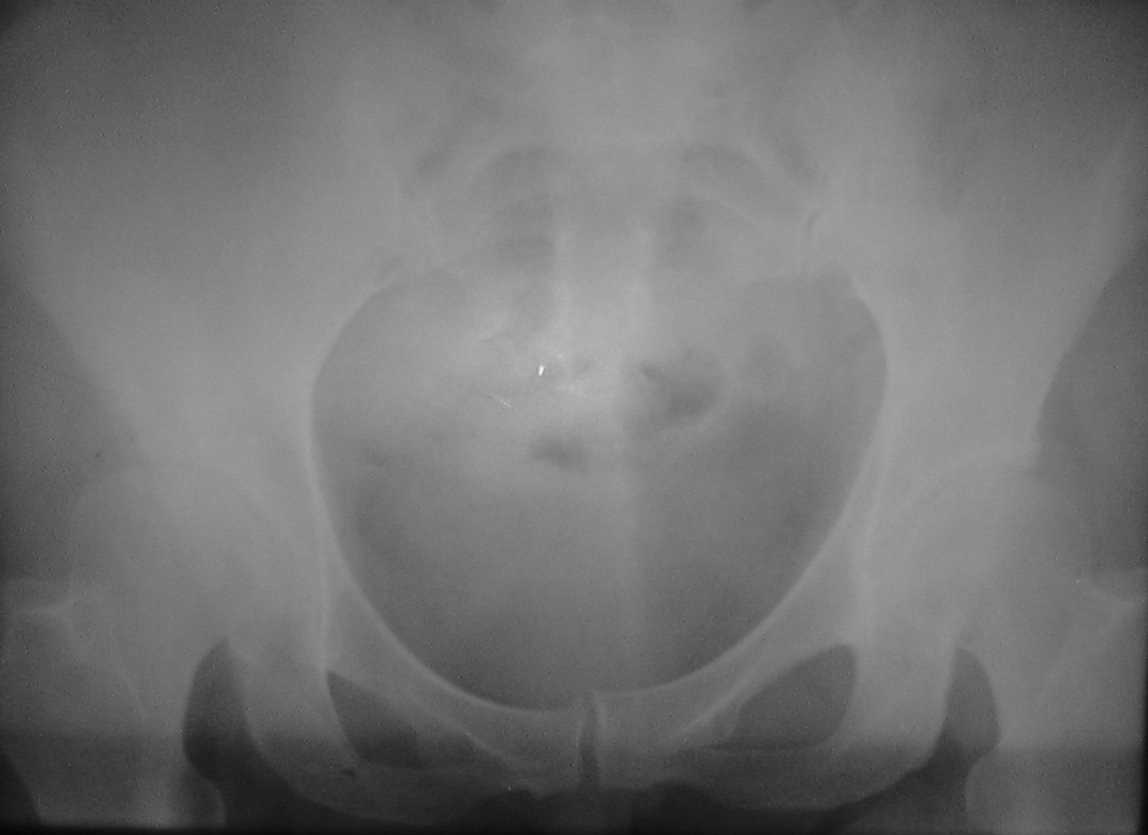

Коллеги .пожалуйста помогите. Представляю КТ нашей операционной сестры.Боли в тазобедренном суставе беспокоят около 2-х лет.В последние2-3 месяца боли усилились, хотя интесивность была умеренная. Продолжала работать проводя,в операционные дни, стоя, по 7-8 часов.Рентгенологом (очень предположительно) выставлен диагноз-туберкулез. Я даже предположительно затрудняюсь поставить диагноз, но, по-видимому, без операции с экспресс-биопсией не обойтись, иначе исход в патологический перелом с центральным вывихом. Три вопроса: 1)Что это? 2)Где лечится? 3)цена вторго вопроса? Больная - гражданка РФ и жена старшего офицера запаса, так что право на лечение в госпиталях МОРФ вроде бы имеет. Но мед. страховки нет. У нас ее просто не выдавали. Заранее благодарен, как я, так и коллектив хирургического отделения.(госпиталь МО г.Тирасполь)

Александр, покажите для наглядности обзорные Ртг таза,а то что-то на седалищную кость не похоже, а второй сустав явно диспластичный. Что примечательного в крови и в клинике указывает на новообразование или специфич. инфекцию?

Спасибо всем,кто откликнулся, высылаю

обзорные снимки таза. Прошу извинения за качество снимков

Ну что уж извиняться, лучше повторить Ртг :-), да и клинику уточнить с акцентом на предыдущ. вопросы. Если нет признаков воспаления - почему не стрессовая киста?